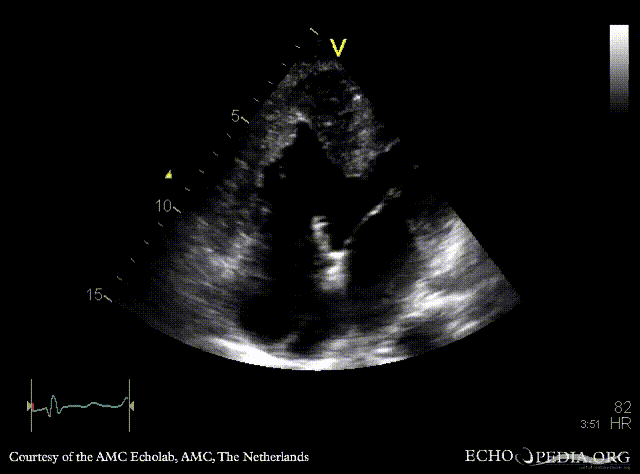

Large VSD, syndrome of Eisenmenger

AMC Echolab, AMC, The Netherlands

A4CH